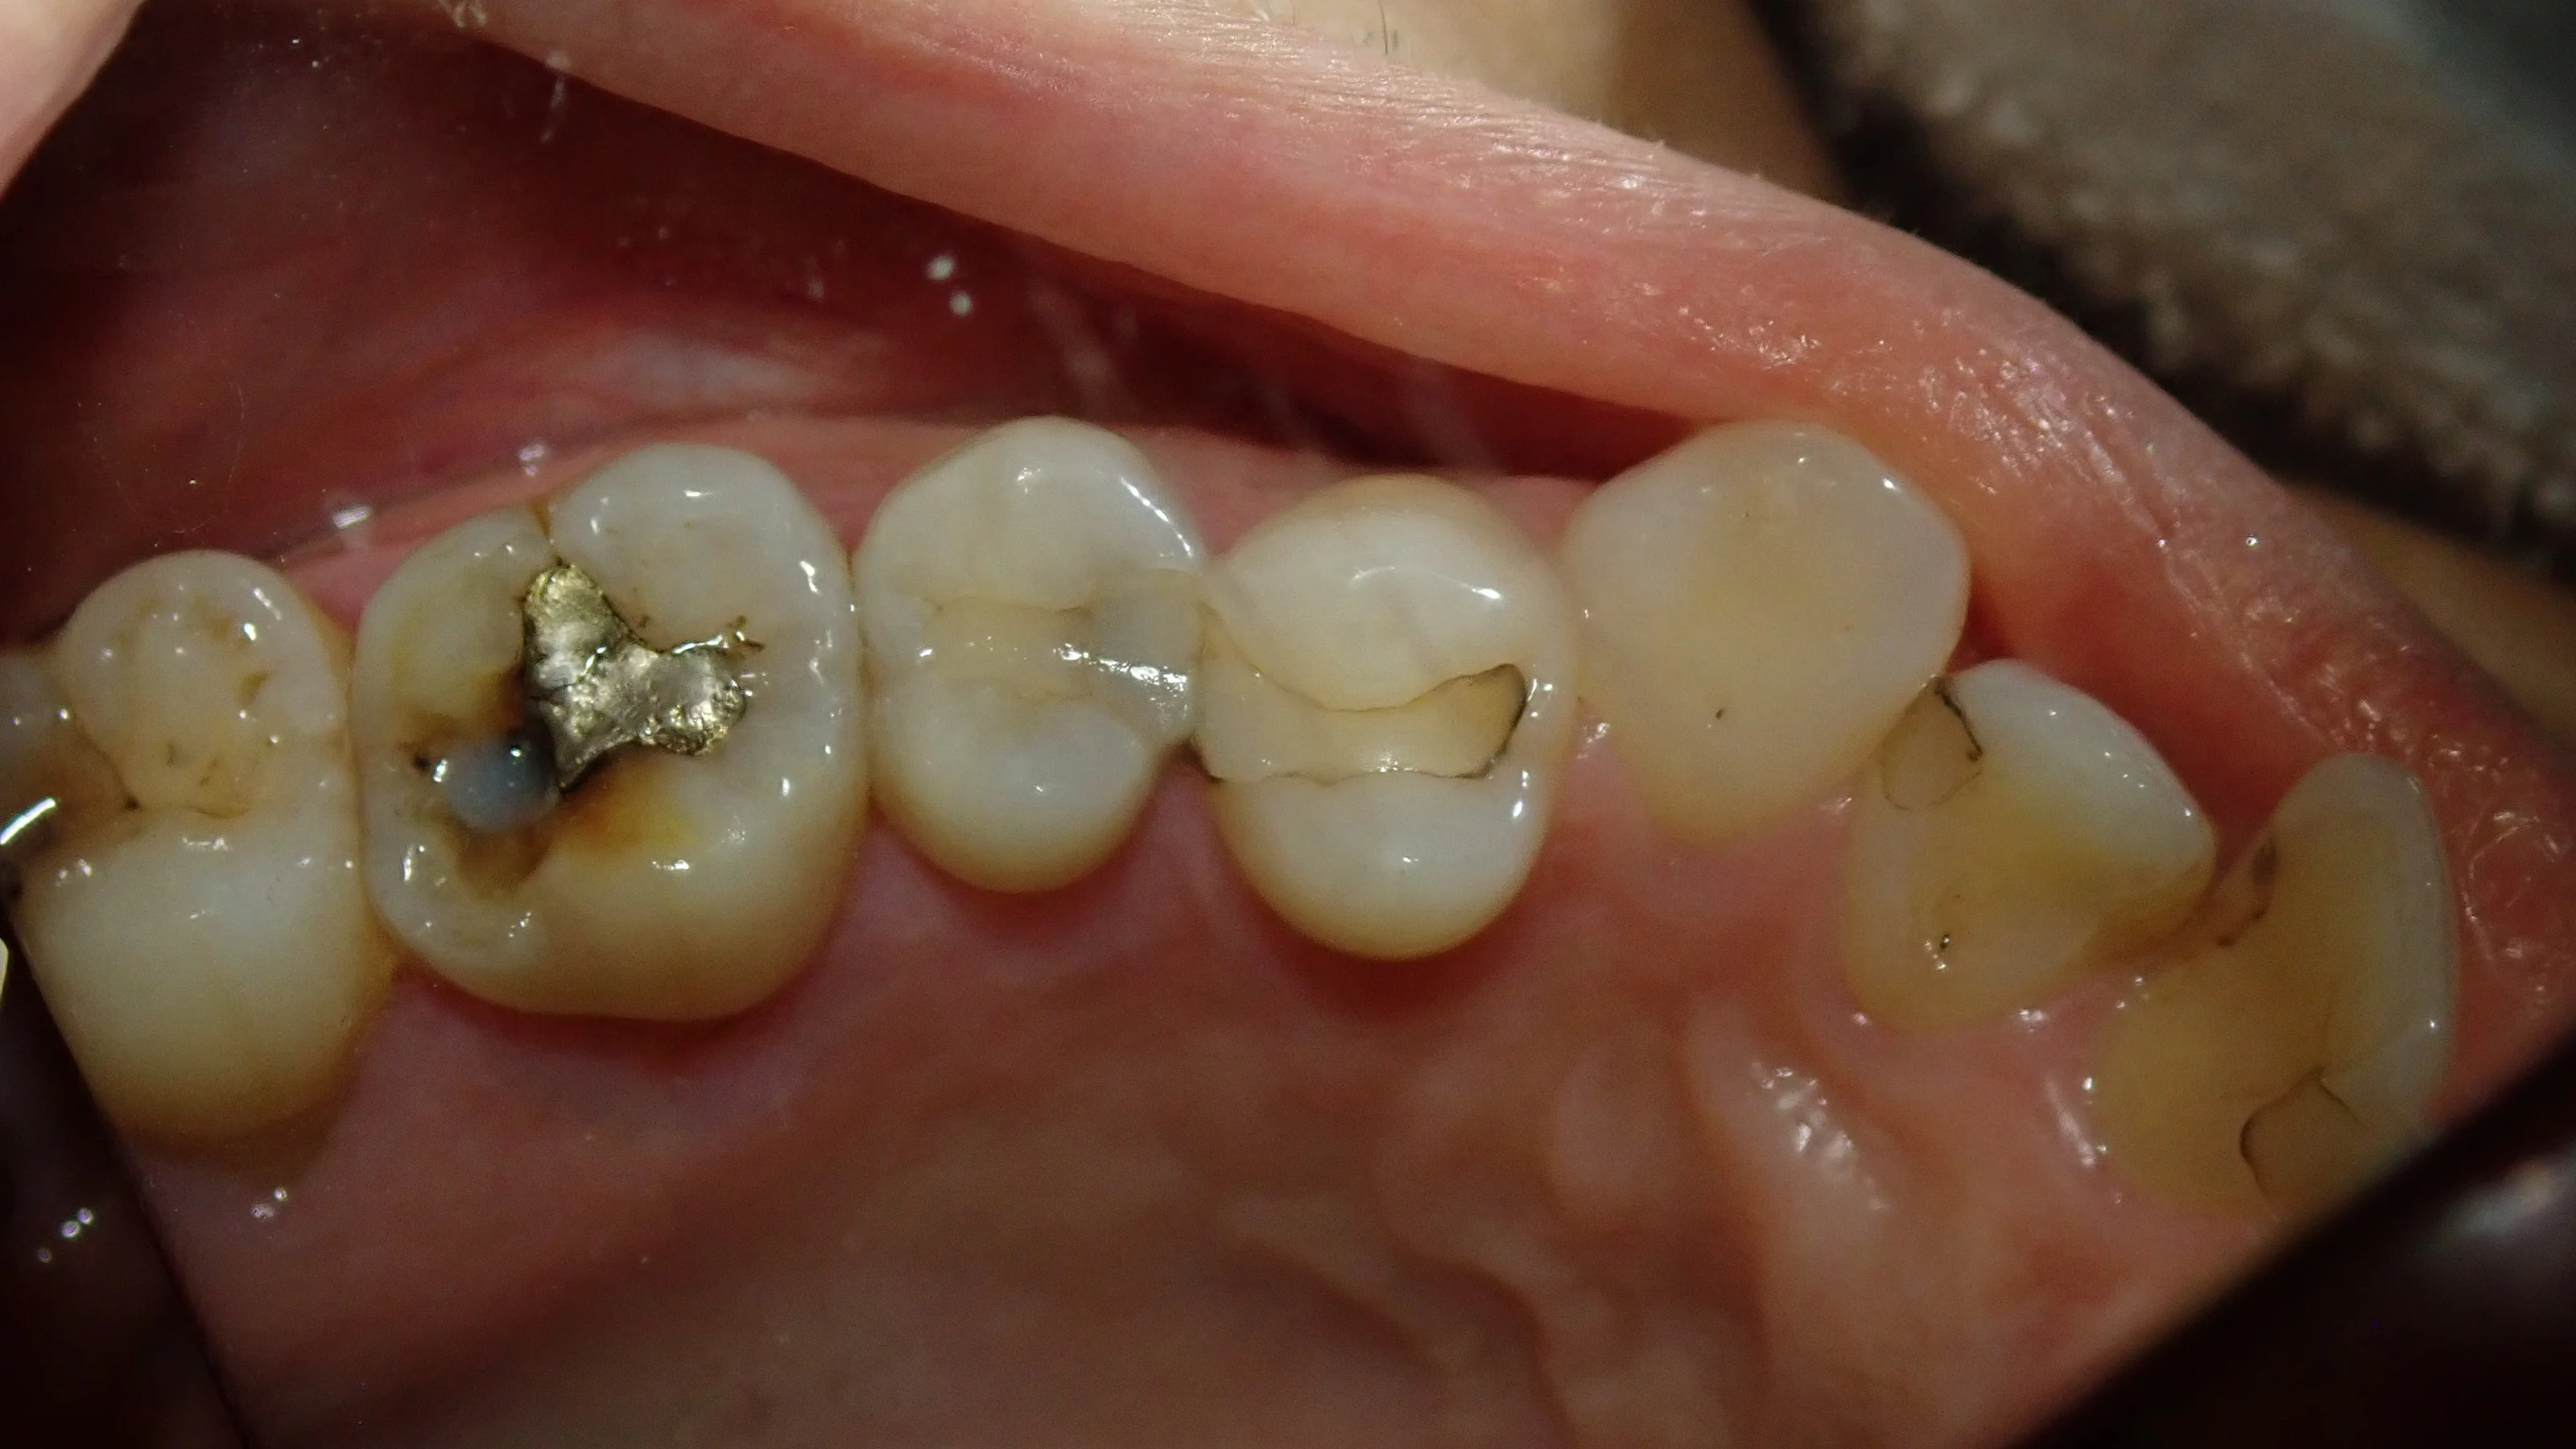

まずはいつもどおり術前から。

今回行うのは画面真ん中の2本の虫歯になります。

元々治療されている白い詰め物の中が黒っぽくなっているのが分かるかと思います。